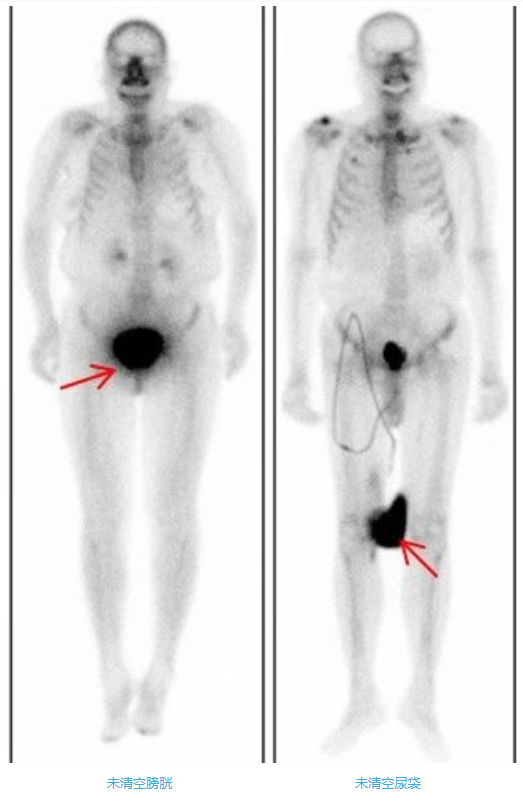

4、多喝水,清空膀胱

注射骨顯像劑后2-5小時,50%-60%顯像劑沉積在骨骼中,剩余的顯像劑或潴留在肌肉或通過尿液排出體外。為了提高骨骼圖像質量,注射骨顯像劑后,需要注射后多飲水(一般500ml-1000ml,受檢者如無明顯不適可增大飲水量)、多排尿。大量小便潴留在膀胱內,會影響骨盆區骨骼的判讀,所以掃描前要清空膀胱。排尿時須避免尿液污染皮膚和衣物。一旦污染了衣物,形成放射性偽影,會影響圖像質量和結果判讀,因此需更換衣物或清洗污染部位后重新進行掃描。如果患者有尿袋,檢查前需要清空尿袋;同樣注意避免污染皮膚和衣物。